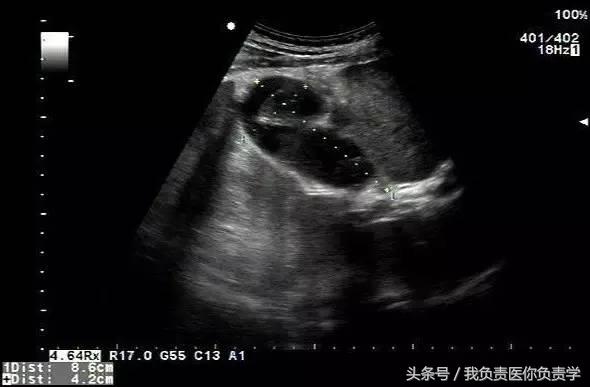

患者女,79岁,晚餐后出现脐周疼痛数小时急诊。患者无发热,实验室检查示白细胞14×109/L,临床考虑阑尾炎,行超声检查所见如下:

图1示胆囊充盈差,囊壁明显增厚,胆囊周围可见无回声环绕分布

图2为高频探头所见,示胆囊壁肝床侧回声中断,周围可见无回声分布

超声诊断为胆囊穿孔,后经手术证实。